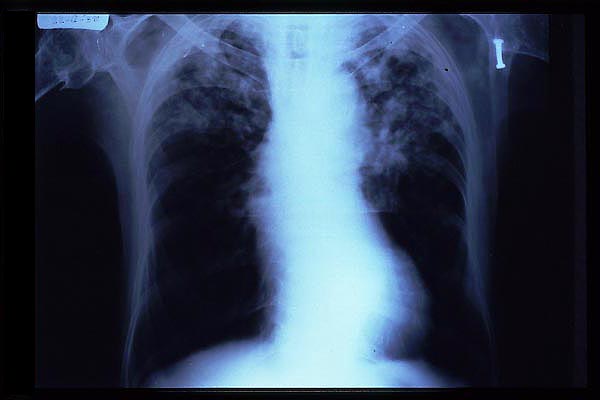

Fibrosis pulmonar. ICC.